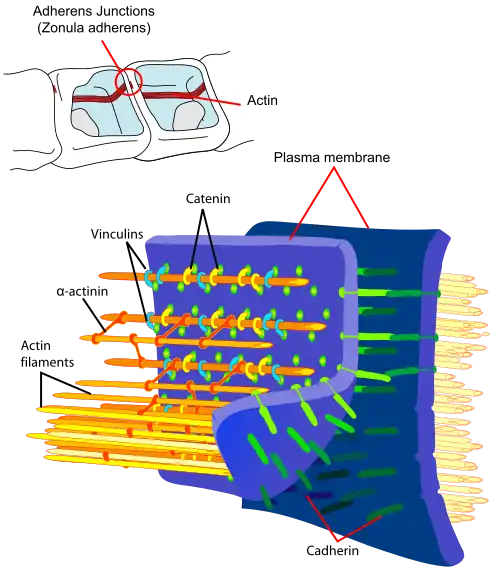

Die Tight Junctions

Die Endothelzellen sind über feste Zell-Zell-Verbindungen, die sogenannten Tight Junctions, miteinander verbunden. Diese Tight Junctions stellen dichte Verbindungen zwischen benachbarten Zellen dar und liefern einen wesentlichen Beitrag für die Schrankenfunktion der Blut-Hirn-Schranke.[24][25] Denn sie dichten den Raum zwischen den Zellen ab und schließen so einen parazellulären Transport, die Passage von Stoffen längs des interzellulären Spaltraums zwischen benachbarten Endothelzellen an diesen vorbei, praktisch aus.[26][27][28]

Mehrere Transmembranproteine, wie Occludin, verschiedene Claudine und Junctional Adhesion Molecules (JAM), verknüpfen die Endothelien im apikalen Bereich der lateralen Zellwände durch umlaufende Proteinbänder in Tight junctions, und unterbinden damit die parazelluläre Passage via Zwischenzellspalt zweier Endothelzellen für größere Moleküle weitgehend.[29] Die einzelnen Protein-Protein-Verbindungen wirken wie parallel verschaltete Sicherungen. Die Endothelzellen der Blut-Hirn-Schranke exprimieren von den 24 bekannten Claudinen nur Claudin-5 und Claudin-12. Claudin-5 wird dabei als wichtigstes Zelladhäsionsprotein der Blut-Hirn-Schranke angesehen.[30] Das Ausschalten (Gen-Knockout) des CLDN5-Gens, das für Claudin-5 codiert, führt bei Mäusen dazu, dass die Blut-Hirn-Schranke für Moleküle mit einer molaren Masse von bis zu 800 g·mol−1 durchlässig wird. Die so genetisch veränderten Tiere verstarben innerhalb weniger Stunden nach ihrer Geburt.[31]

Durch die Fixierung der Endothelien wird zugleich deren Ausrichtung in zwei sehr unterschiedliche Seiten gewährleistet: in die luminale, dem Blut entgegengerichtete Seite und die abluminale, dem Gehirn zugewandte Seite.[6]